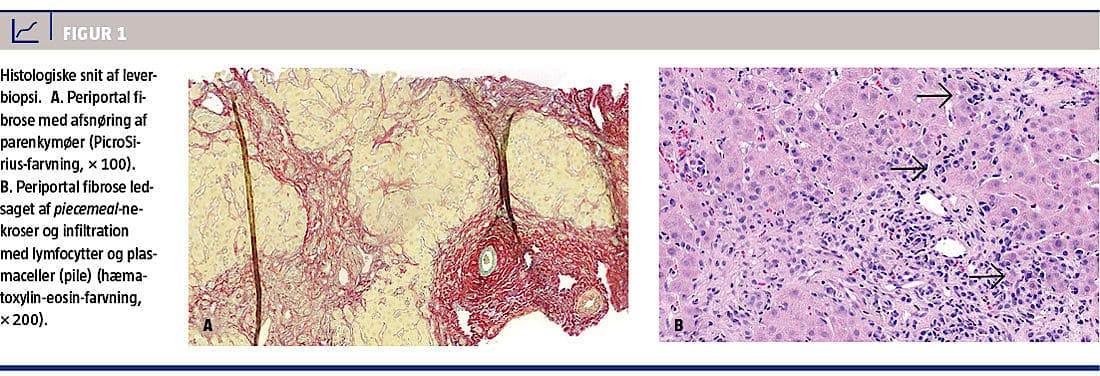

Efter to måneder var BILI-niveauet normaliseret, men pga. vedvarende parenkymatøs leverpåvirkning med et ALAT-niveau på 222 E/l blev der foretaget leverbiopsi. Denne viste kronisk hepatitis med fibrosegrad 3 og moderat inflammatorisk aktivitet, hvilket var foreneligt med AIH (Figur 1). Med baggrund i biopsisvaret blev der iværksat behandling med budesonid 9 mg × 1 dagligt, hvilket normaliserede levertallene i løbet af få uger.

I sjældne tilfælde ses en fulminant form af AHA med panlobulær nekrose. Ved AHA udvikles der ikke fibrose, og kroniske former kendes ikke. AIH er en kronisk inflammatorisk leversygdom, der histologisk minder om AHA. Den adskiller sig dog ved fibrose i relation til den periportale inflammation og nekrose, og ubehandlet progredierer AIH til cirrose. Patienten i sygehistorien opfyldte de internationale kriterier for diagnosen AIH (autoimmun prædisposition, typisk biokemi, autoimmun serologi og karakteristisk histologisk billede) [2]. Amlodipininduceret medikamentel hepatitis blev udelukket pga. den stabile behandling igennem en årrække.